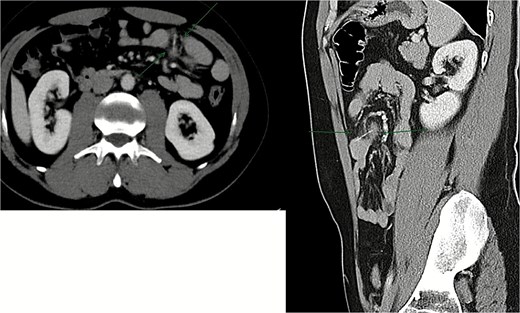

Contrast-enhanced CT of the abdomen revealed a radiopaque linear foreign body measuring approximately 3 cm lodged within a jejunal loop, penetrating the bowel wall into the adjacent mesenteric fat. Prominent fat stranding was present, without evidence of free intraperitoneal air, bowel obstruction, or abscess formation (Fig. 1).

Contrast-enhanced CT scan showing ~3 cm radiopaque linear foreign body lodged within a jejunal loop, penetrating the bowel wall into adjacent mesenteric fat.